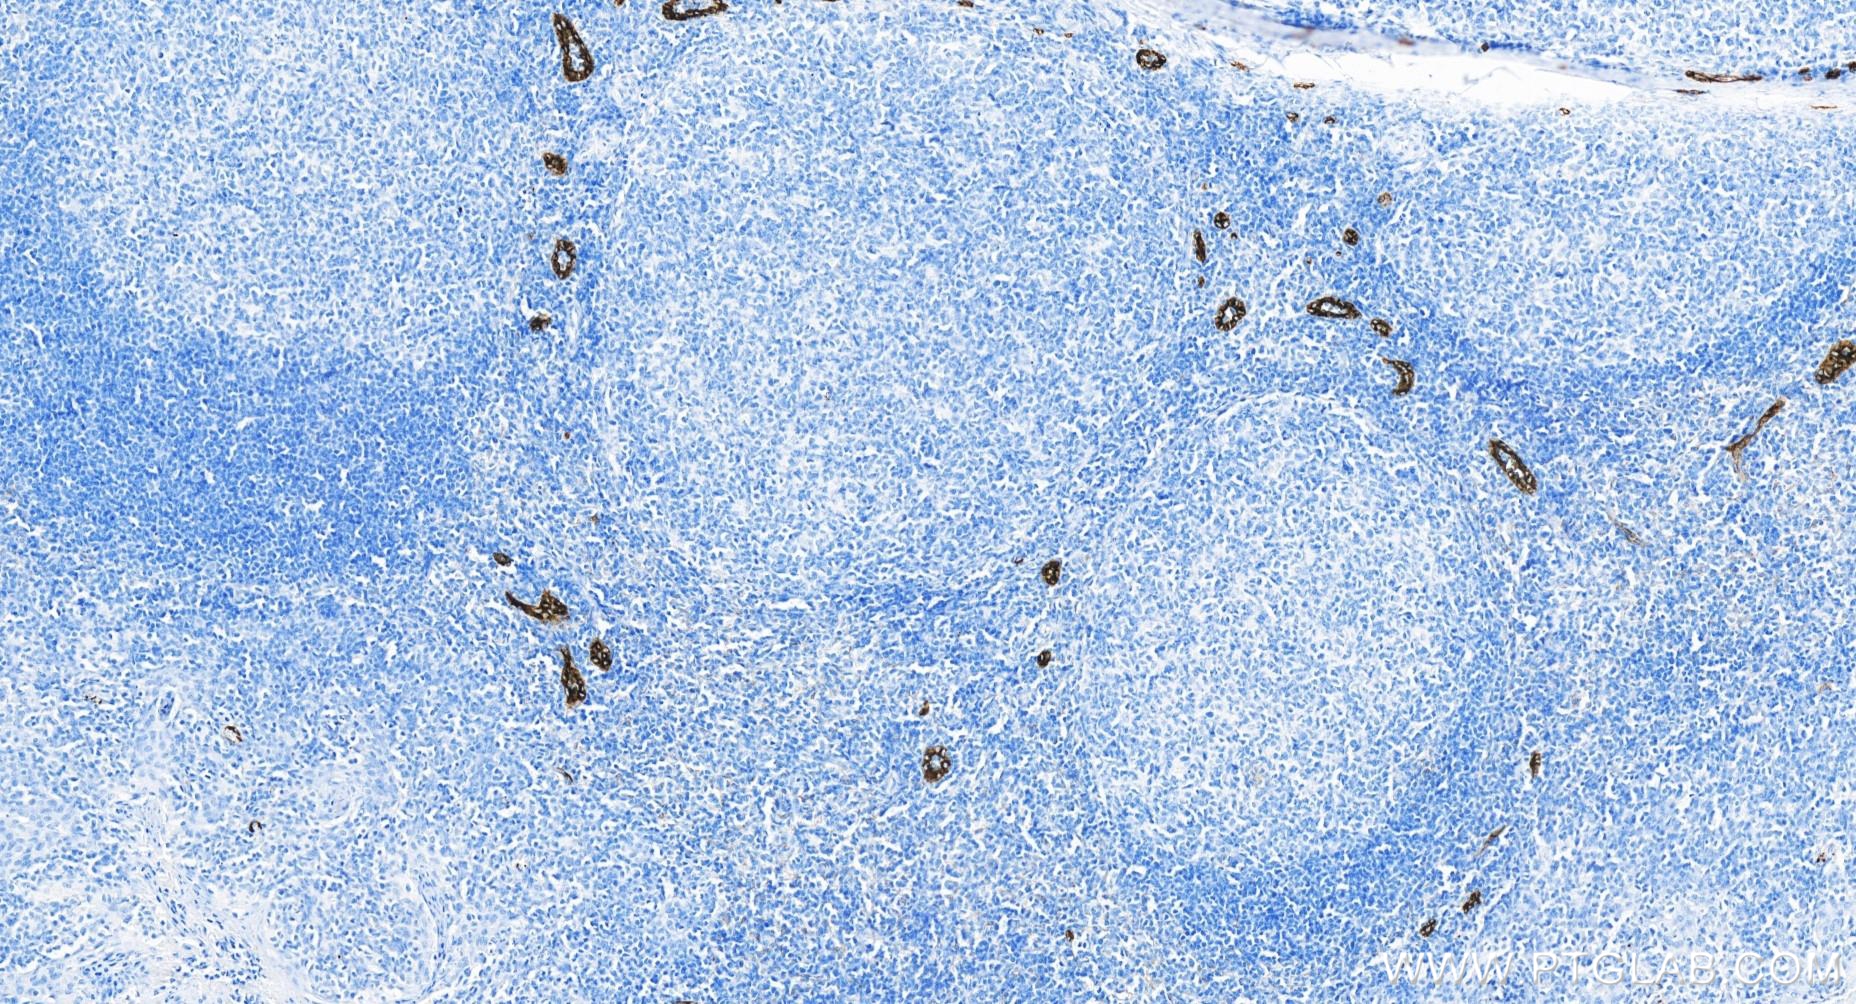

| Positive IHC detected in | human tonsillitis tissue, mouse spleen tissue, rat spleen tissue Note: suggested antigen retrieval with TE buffer pH 9.0; (*) Alternatively, antigen retrieval may be performed with citrate buffer pH 6.0 |

| Immunohistochemistry (IHC) | IHC : 1:400-1:1600 |